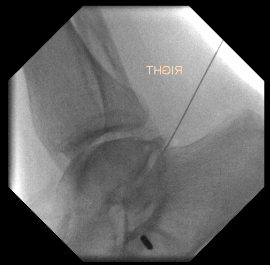

Arthroscopic subtalar arthrodesis

Lateral / supine position with lateral portals

Prone position with posterior +/- accessory lateral portals

Technique

Vumedi posterior arthroscopic subtalar arthrodesis video

Arthroscopic techniques lateral arthroscopic subtalar arthrodesis video

JBJS Essential Techniques Posterior Arthroscopic Subtalar PDF